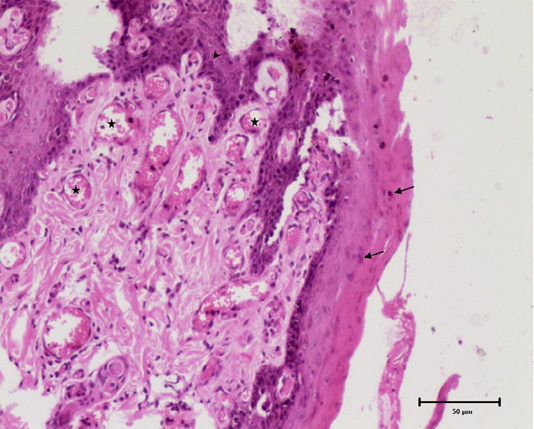

Histomicrograph showing diffuse epidermal hyperplasia with parakeratosis (arrows), broad and elongated rete pegs (arrowhead) and neovascularization of superficial dermis (star). H and E, 10x.